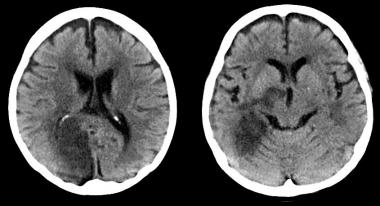

Tanto el cabeceo de la pelota como los traumatismo involuntarios durante el juego se asociaron a un aumento de síntomas neurológicos moderados a severos. Neurology, 1º de febrero de 2017

¿Por qué hay pacientes con ACV isquémico que no reciben tratamiento con tPA intravenoso?

En una gran cohorte de EEUU, una cuarta parte de los pacientes con accidente cerebrovascular isquémico e indicación para tPA-IV no recibieron la medicación. Se asoció con edad avanzada y con el sexo femenino, entre otros factores. Neurology, 14 de septiembre de 2016